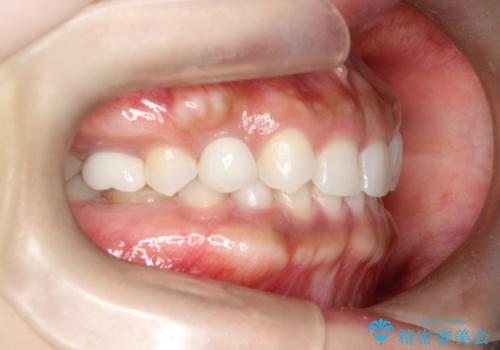

- 後続永久歯が欠損した患者様です。

矯正治療にて歯並びを改善したのち、インプラントにて咬合回復を行う治療計画としました。

捻転が強い部分だけはワイヤーの部分矯正で対応しております。